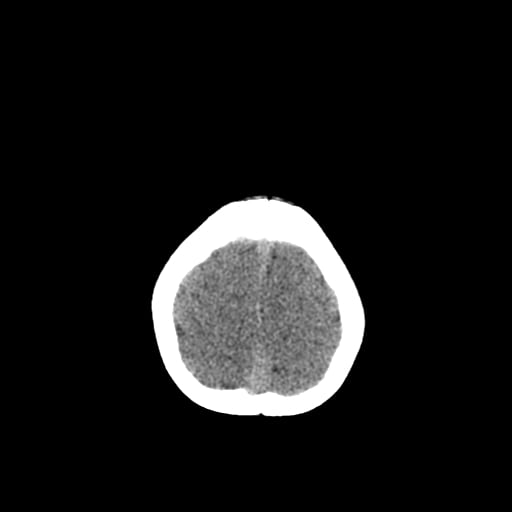

Age: 1

Sex: Male

Indication: Fall